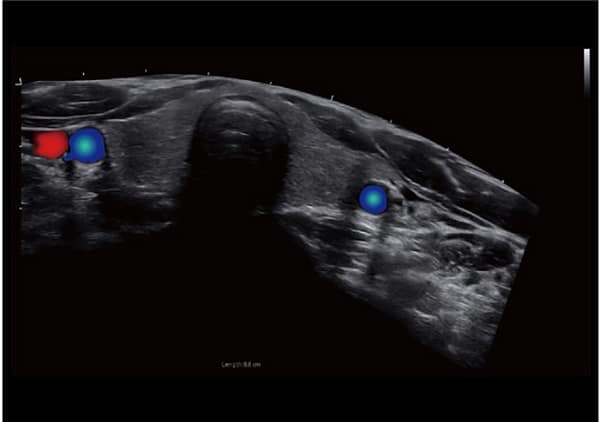

- Hình Ảnh Toàn Cảnh Màu: Phóng to vùng quét và cung cấp nhiều thông tin về màu sắc, đặc biệt hữu ích cho việc phân tích mạch máu lớn.

- SonoColor và SonoContrast: Cung cấp phân tích dòng định lượng và độ nhạy cao hơn, thích ứng với mọi loại đầu dò.